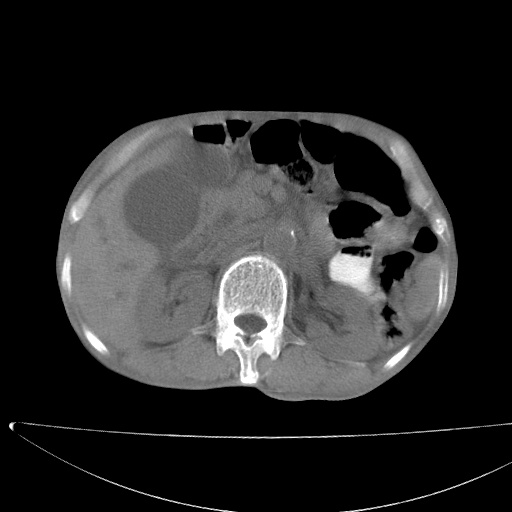

标题: CT17147:男70岁,上腹部不适1月。 [打印本页]

患者男70岁,上腹部不适1月。8年前有胃癌手术史。余病史不祥。

考虑胃癌复发并腹腔内淋巴结转移,胆总管受侵。

考虑胃窦癌肝门区淋巴结转移!

肝门区占位性病变并肝内胆管扩张。

小网膜囊区及腹膜后肿大淋巴结。